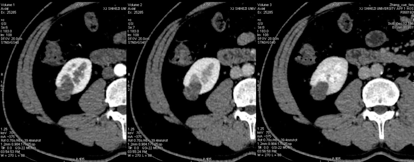

4. 三期冠状位测量结果显示同样结果;而肝实质、肾脏髓质均有明显强化。

最终诊断:肾囊肿。 病例讨论:能谱分析功能可以解决临床中有争论或者诊断不明确的情况。尽管常规显示中似乎有强化的存在,但不能确切诊断。该病例通过碘含量的测量,明确了病灶没有强化。为最终诊断定下了重要的线索。 备注:该病例来自石河子大学医学院附属医院